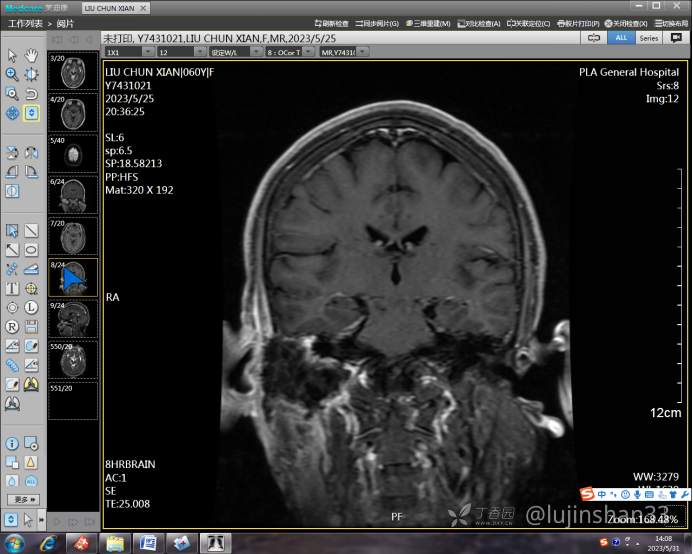

(2023-05-15 10:00,本院)行磁共振(颅脑)检查提示:右侧乳突区异常信号,考虑恶性、软骨来源肿瘤,软骨肉瘤可能性大。(集体讨论意见);脑内散在多发缺血灶。

(2023-05-12 10:15,本院)行CT(颅脑)检查提示:右侧颞骨广泛骨质破坏,伴巨大软组织肿块,性质待定,考虑肿瘤性病变,颈静脉球瘤?软骨源性肿瘤?请结合临床及病理进一步明确。